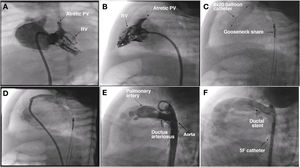

We present the case of a boy aged 15 months with a prenatal diagnosis of pulmonary atresia with intact ventricular septum who underwent pulmonary valve perforation and balloon valvuloplasty with an 8 mm balloon at 9 days post birth (Fig. 1A–D; Appendix B, videos 1–3). At 30 days, due to persistent desaturation, the decision was made to perform percutaneous ductal stenting, since this was less invasive compared to other techniques used to increase pulmonary flow. The procedure, guided by ultrasound, consisted in the delivery, via the left femoral artery and using a 5 F introducer, of a drug-eluting stent (Onyx Frontier, Medtronic, USA) measuring 4.5 × 12 mm to the ductus arteriosus (Fig. 1E and F; Appendix B, videos 4 and 5). Five days after the procedure, the patient experienced vomiting, and the abdominal ultrasound scan used for initial assessment revealed a mass in the left groin, with subsequent Doppler and angio-CT scans allowing visualization of a pseudoaneurysm at the level of the left common iliac artery (Fig. 2A–F).

(A) and (B) Right ventriculogram, anteroposterior and lateral views showing pulmonary valve atresia (7.5 mm ring). C) Pulmonary valvuloplasty performed with a TYSHAK MINI® (NuMED) 8 × 20 mm balloon catheter advanced on a 0.0014 coronary guidewire, which traversed the ductus arteriosus to the aorta supported by a gooseneck snare. (D) Angiographic confirmation of preserved pulmonary flow after valvuloplasty. (E) Lateral aortogram showing patent ductus arteriosus and filling of right chambers. (F) Aortogram following stent placement.

PV, pulmonary valve; RV, right ventricle.